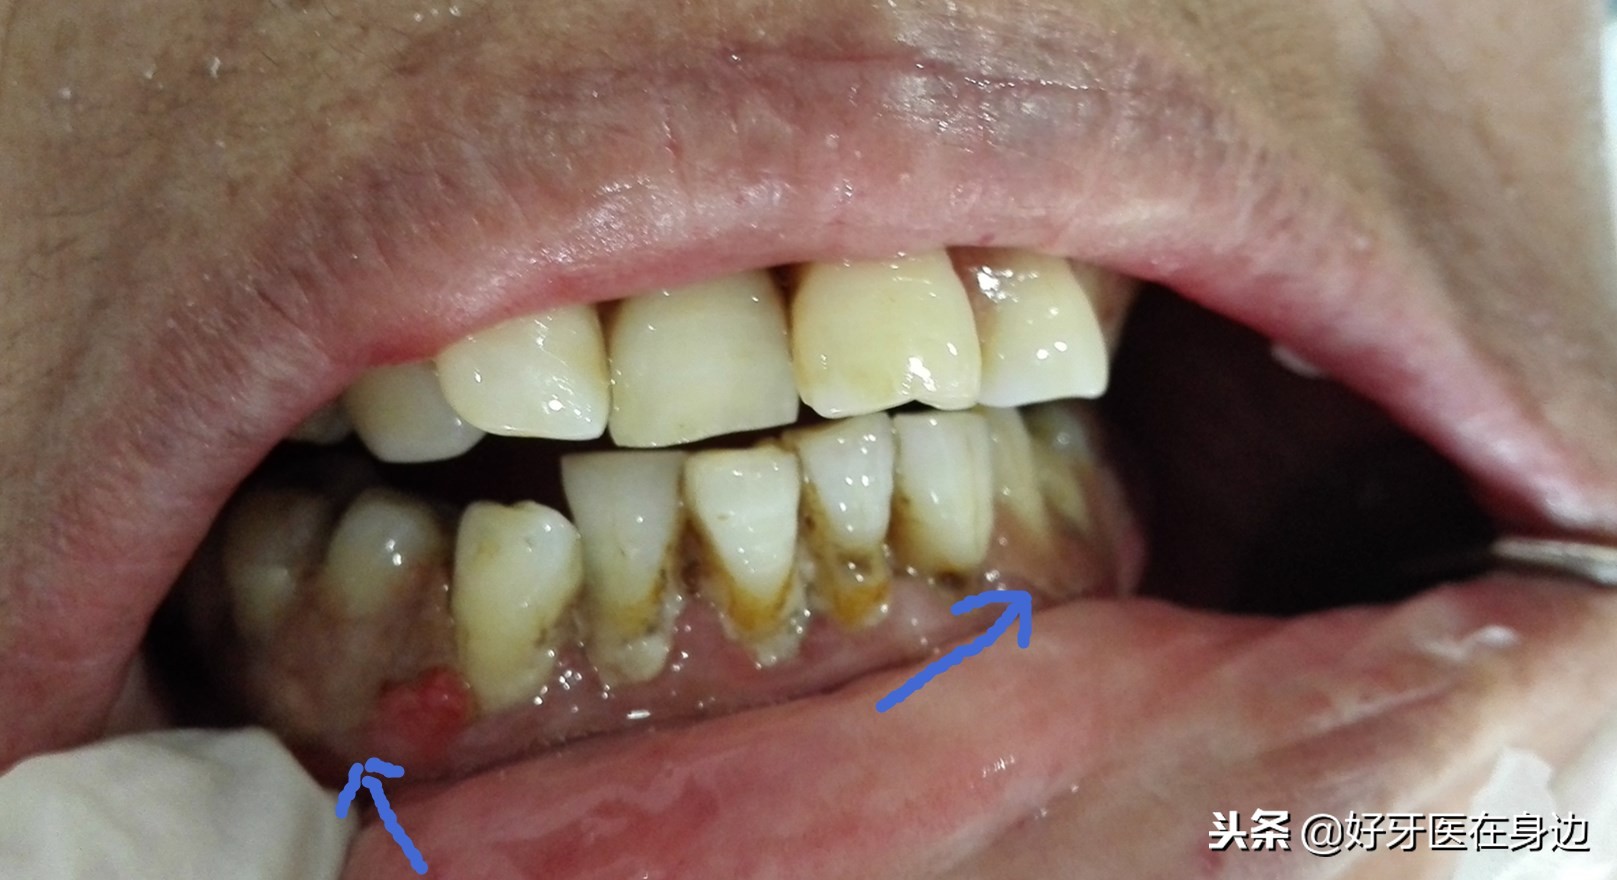

下颌不良修复体

不良修复体导致的牙龈红肿